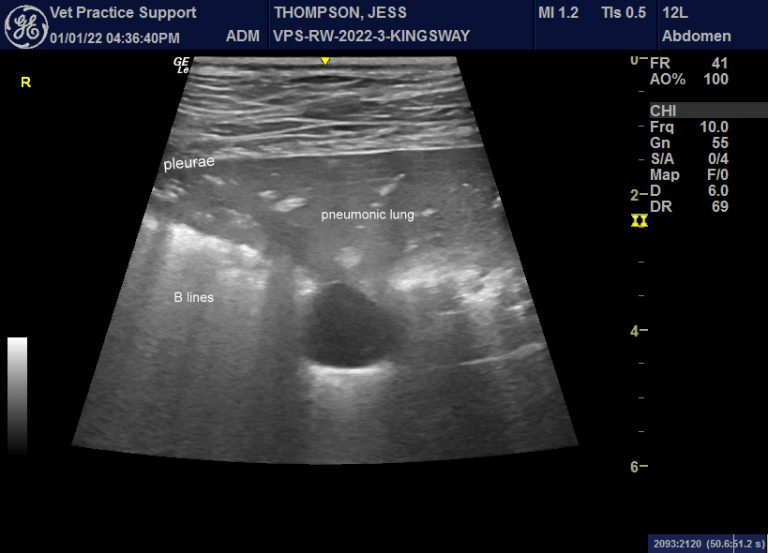

From www.vetpracticesupport.com

Pneumonia in dogs gastrointestinal presenting signs Vet Practice Support What Is Pneumonia In Dogs Pneumonia is an illness that bothers both humans & dogs. You can usually recognize it by your dog coughing, and having trouble to breathe. Viruses such as canine distemper virus,. Different types of pneumonia, such as aspiration pneumonia, can. Pneumonia is irritation and inflammation within the lungs that results in the buildup of fluid within the air sacs. Pneumonia is. What Is Pneumonia In Dogs.